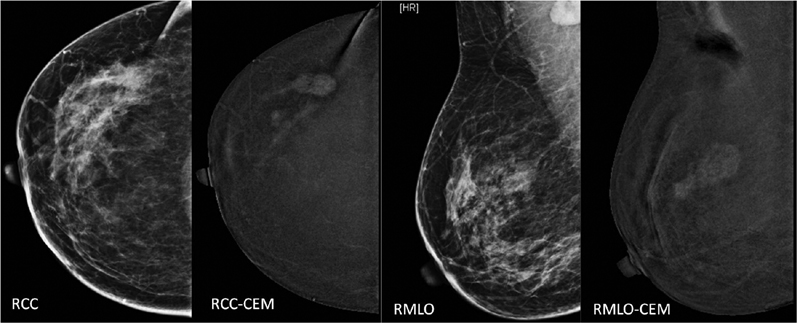

A recent entry in breast imaging is contrast-enhanced mammogram (CEM).[8]

Iodinated contrast is introduced intravenously, and subsequently, low and high-energy X-ray images are obtained. These images are then post-processed to get subtracted images. The post-processed images show only contrast enhancement within the breast, masking background parenchymal density ([Fig. 2]). This new technique has many promising advantages: it is cheap, fast, and many existing mammography machines can be upgraded to incorporate this technique. It is especially useful in locations where access to breast magnetic resonance imaging (MRI) is limited. This technique is also described as poor women's MRI. However, being a fairly recent technology, many studies are occurring around the world for its use in different indications.

| Fig.2:Mammogram (= low-density image on CEM) and processed contrast-enhanced images of the right breast in CC and MLO views, showing enhancement of lesion in the upper outer quadrant with suppression of background parenchymal density. Adjacent satellite lesion is better seen on contrast image (CEM) on CC view. CC, craniocaudal; CEM, contrast-enhanced mammogram; MLO; mediolateral oblique.

| Fig.2:Mammogram (= low-density image on CEM) and processed contrast-enhanced images of the right breast in CC and MLO views, showing enhancement of lesion in the upper outer quadrant with suppression of background parenchymal density. Adjacent satellite lesion is better seen on contrast image (CEM) on CC view. CC, craniocaudal; CEM, contrast-enhanced mammogram; MLO; mediolateral oblique.